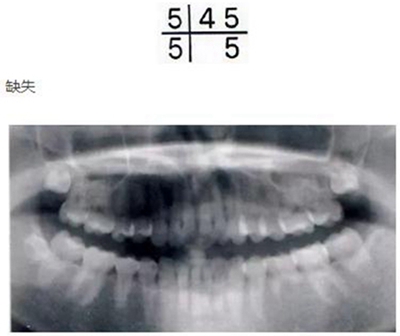

乳牙的晚期殘存(恒牙的先天性缺失)

[原因不明的多顆恒牙先天性缺失病例(17歲)]右下E殘存,

2.jpg

ccb43bd9003a4ecb548521c21197e7a9_6364219042849874312265982.jpg

3b80ba33471e86d989336f23371e34b3_6364219042867061816751123.jpg

解說(shuō) 確認(rèn)是否是恒牙的先天性缺失

乳牙的晚期殘存有可能是恒牙的先天性缺失引起的。恒牙的先天性缺失有1、2顆牙缺失,也有好幾顆牙同時(shí)缺失的情況。數(shù)顆恒牙的缺失有可能是特定的先天性疾?。ㄍ馀邔影l(fā)育不良綜合征*1、色素失禁癥*2)引起的,需要加以注意。

好發(fā)部位位于第三后磨牙、上頜側(cè)切牙、上下頜第二前磨牙。根據(jù)有關(guān)研究,切牙從上頜遠(yuǎn)中側(cè)和下頜近中側(cè)開(kāi)始退化。磨牙無(wú)論上下頜都是從遠(yuǎn)中側(cè)開(kāi)始退化,有一定的規(guī)律。

缺失部分有空隙的話(huà),可以用殘存齒進(jìn)行修補(bǔ),但是根據(jù)上下頜關(guān)系也有不能采用這種方式病例。如果僅靠正畸治療無(wú)法解決問(wèn)題的話(huà),將來(lái)有可能在缺損部植入修復(fù)物和假牙,因此需要事先告知父母讓其有心理準(zhǔn)備。